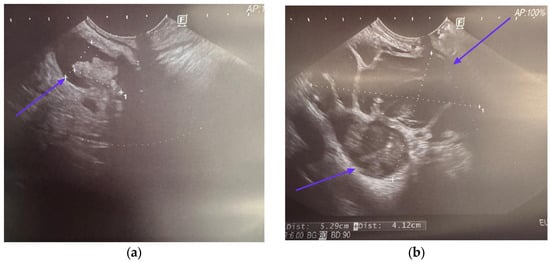

5. Endoscopic Ultrasound in Detecting Malignancy in IPMN